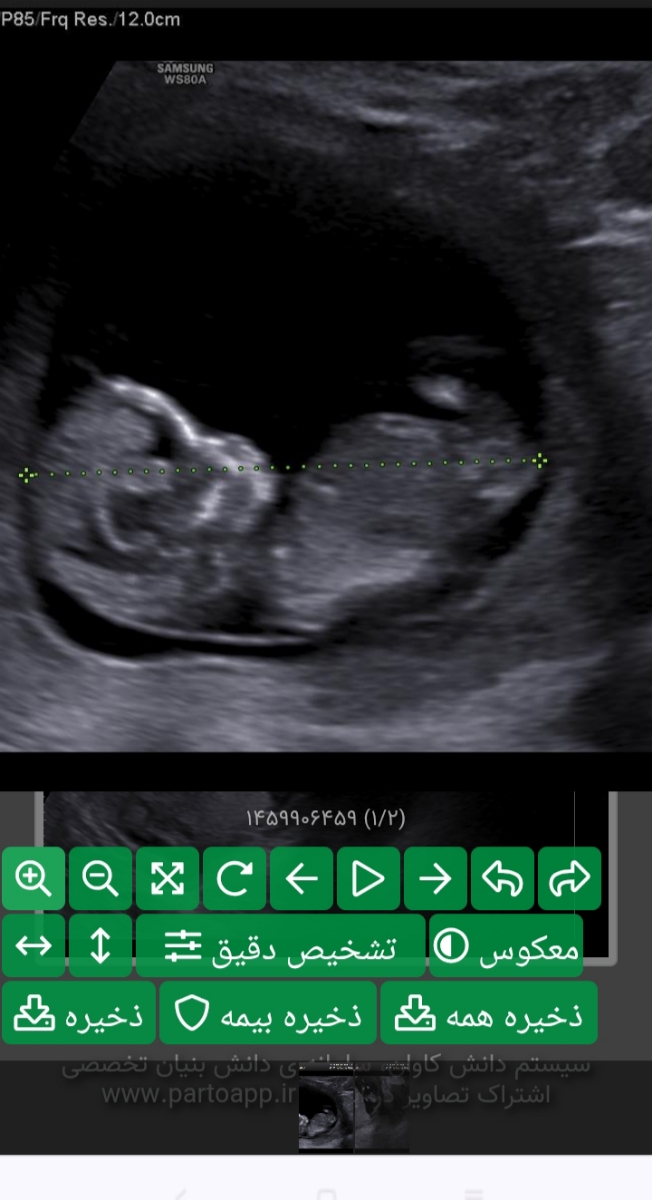

سلام خدمت خانم دکتر و خانمای عزیزم.. میشه جواب NT رو تفسیر کنید و جنسیت رو تشخیص بدین ممنون میشم

سلام عزیزم جفتت پایینه رعایت کن تا انومالی بره بالا

جان دلم هماتوم دارید و جفت هم پایین است شیاف پروژسترون 400 به صورت مقعدی شبی یکی استفاده کنید استراحت رو به مطلق داشته باشید نزدیکی نکنید دخول چه واژینال چه مقعدی کاملا متوقف گردد و شخص شما به ارگاسم نرسید و تحریک و دستکاری نوک سینه ها انجام نشود تلاش کنید تا دچار یبوست نشوید از سرویس بهداشتی فرنگی استفاده نمایید و دوش آب گرم طولانی مدت نگیرید تا هفته 18 که زمان سونوگرافی مجدد است شیاف را. ادامه دهید

مابقی موارد طبیعی است ولی جهت تفسیر صحیح باید منتظر بخش خون غربالگری باشیم